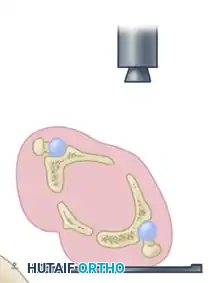

Technique for Measuring Roof Arcs

The roof arc is measured across the three standard radiographic views. A vertical reference line is drawn through the geometric center of the acetabulum. A second line is drawn from the geometric center to the point where the fracture line intersects the intact acetabular roof. The angle formed between these two lines is the roof arc.

- Medial Roof Arc: Measured on the AP pelvis view. Evaluates the superior-medial aspect of the dome.

- Anterior Roof Arc: Measured on the Obturator Oblique view. Evaluates the superior-anterior aspect of the dome.

- Posterior Roof Arc: Measured on the Iliac Oblique view. Evaluates the superior-posterior aspect of the dome.